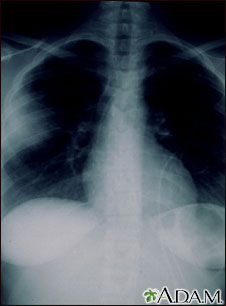

La aspergilosis es una infección micótica en la cual un hongo invade y destruye el tejido. Este tipo de infección normalmente se presenta en individuos inmunocomprometidos. En este caso, la radiografía de tórax muestra que el hongo ha invadido el tejido pulmonar. En una radiografía, los pulmones generalmente se ven como áreas oscuras y la opacidad en el lado izquierdo de esta radiografía se debe a la presencia del hongo.